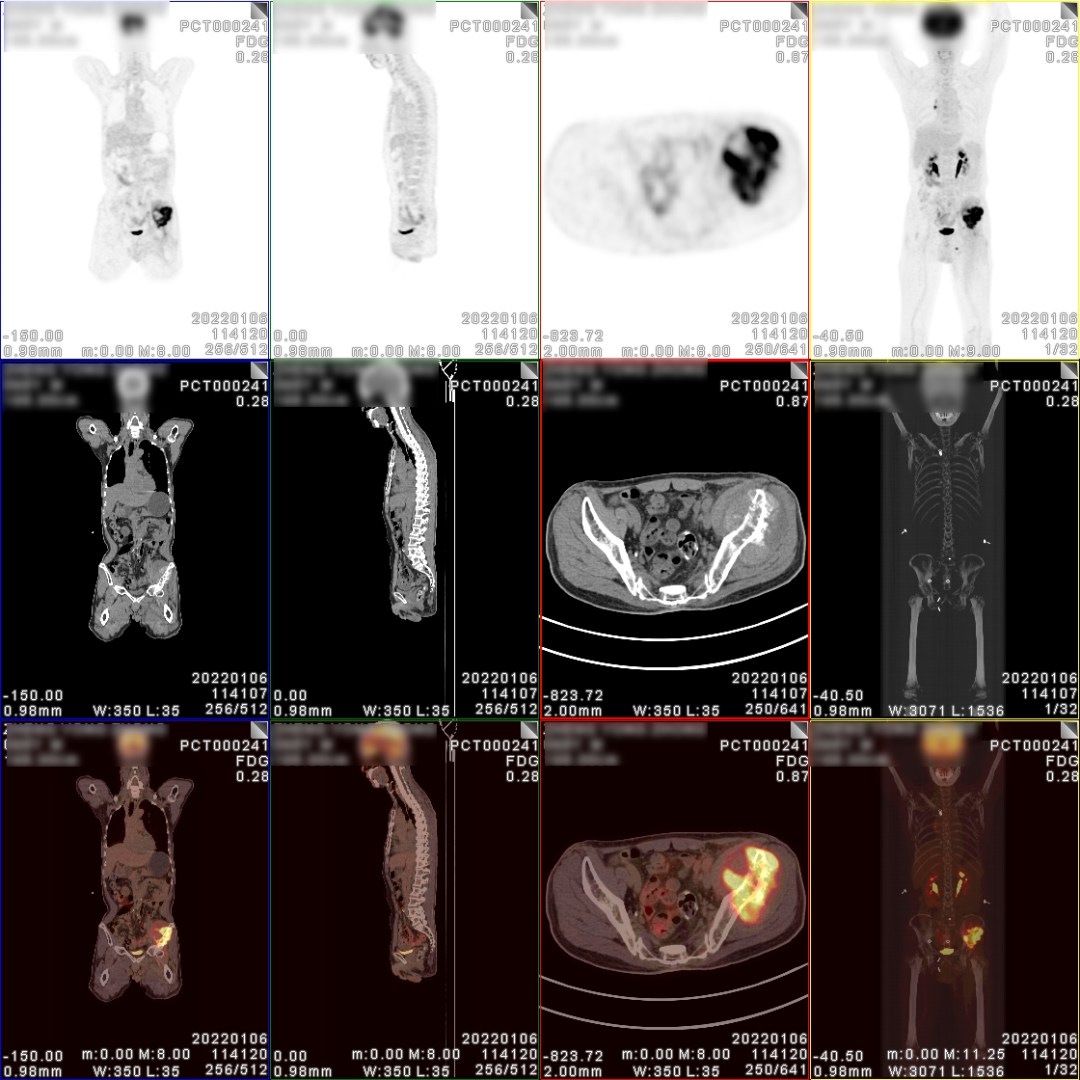

PET/CT检查图像

图片

PET/CT诊断:

1、乙状结肠癌术后、化疗后,肠道吻合口区未见明显恶性肿瘤征象;

2、盆腔内左侧髂外血管旁肿大淋巴结,代谢稍增高,建议临床追踪以排外淋巴结转移灶的可能;

3、右肺转移癌术后,右肺中、下叶支气管残端区未见明显恶性肿瘤征象;残留右肺上叶后段多个小结节影及斑片影,代谢稍增高,多考虑肺转移灶;

4、右侧肺门区肿大淋巴结,代谢增高,考虑淋巴结转移灶;

5、左侧髂骨及左侧坐骨骨质破坏,代谢增高,考虑骨转移灶,左髂骨病灶侵犯周边软组织。